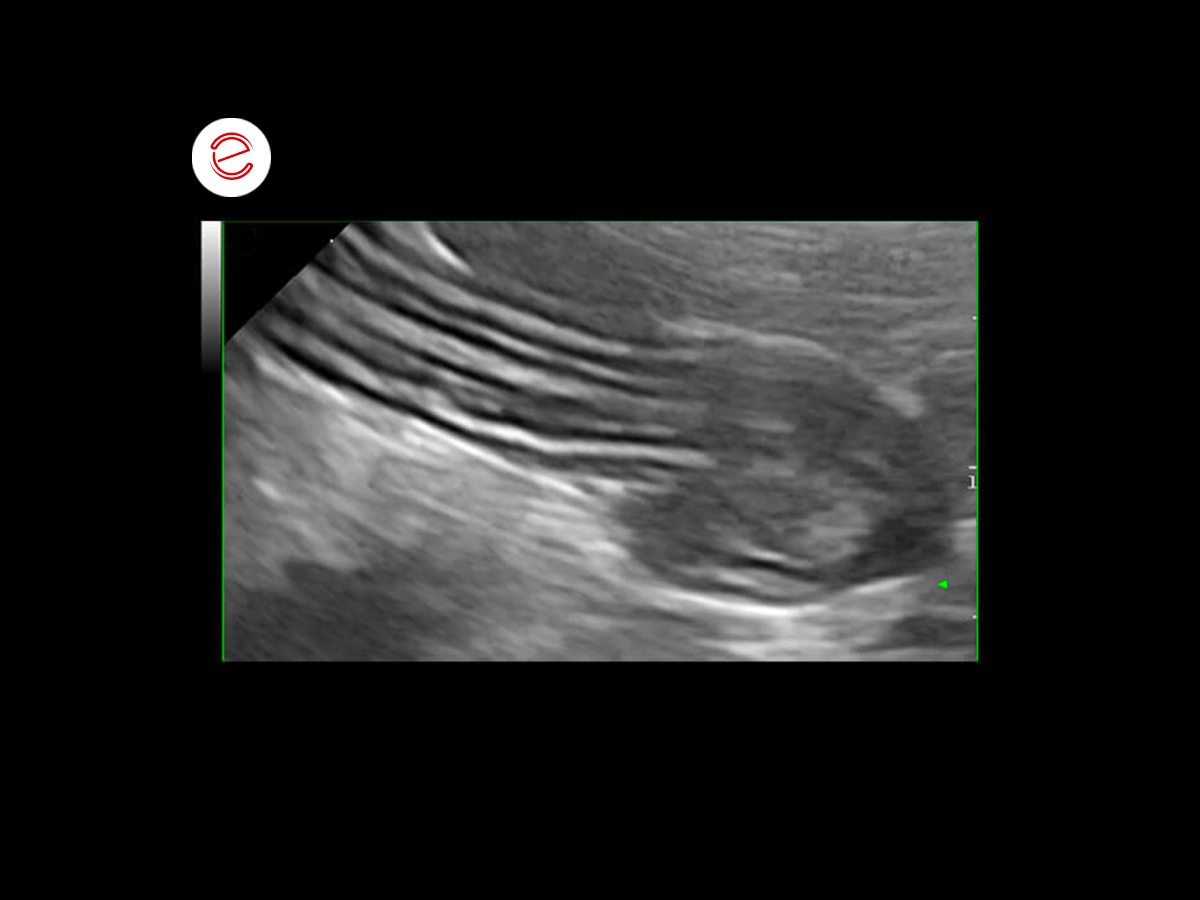

Questa immagine ecografica mostra la stratigrafia fisiologica di un’ansa digiunale, che presenta 5 strati.

Questa immagine ecografica mostra la stratigrafia fisiologica di un’ansa digiunale, che presenta 5 strati.